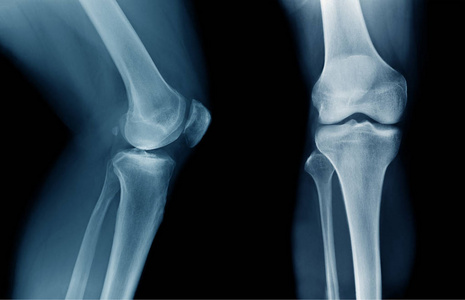

骨科大夫坐门诊,最喜欢的就是拍X光片,X光片经济,快捷,通过X光片,骨科医生可以发现骨科大多数疾病的症结所在,但是有时候,X光片的报告也会给患者带来一些误导,最为常见的误解就是大多数人患者的 X片报告里面都会有这样一句话:某某部位可见“骨质增生”表现。

骨质增生最常见的部位是人体负重的大关节,尤其膝关节,其次是人体脊柱关节,尤其是颈腰椎,除此之外,还有负重的跟骨骨刺也非常常见。这些关节要么是活动度很大,要么就是负重很多的部位,也就是应力集中区域。因此这些区域最常发生骨质增生,尽管有那么多人检查出有骨刺,但并非所有长骨刺的人都有临床症状,且临床症状严重程度也与骨刺的大小、多少不一定呈正比,通常也都不需要手术治疗。

膝关节骨质增生:膝关节骨刺大多数情况下是不需要治疗的,尤其膝关节关节面边缘及中间增生的骨刺,只有当骨刺引起关节软骨磨损,或者形成游离体卡主关节的时候,才需要手术治疗,通常情况下,保守治疗即可缓解症状。